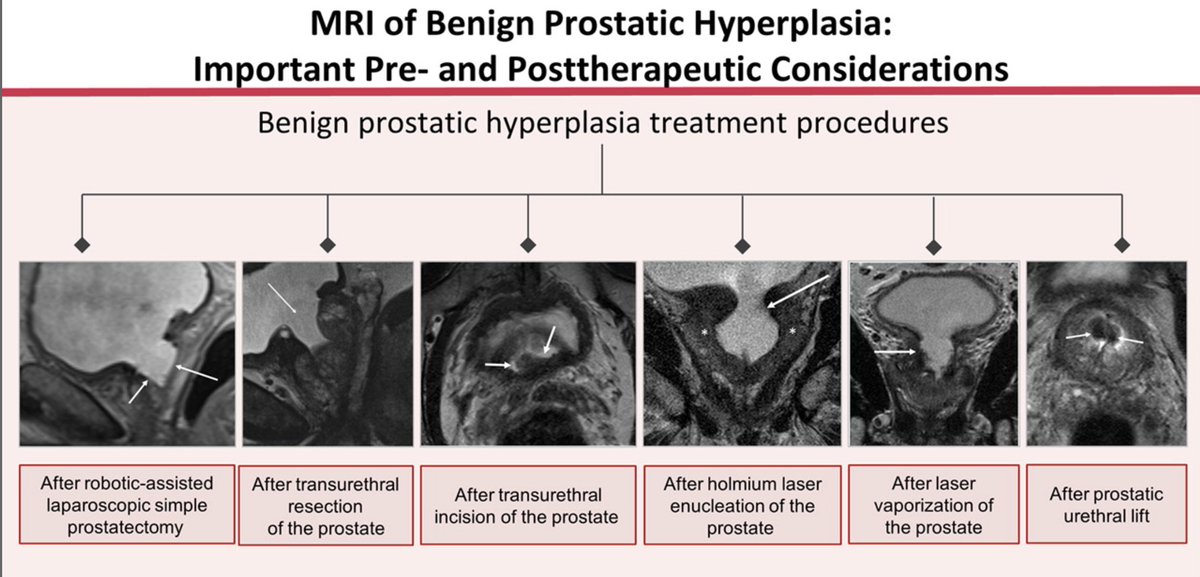

"MRI of Benign Prostatic Hyperplasia: Important Pre- and Post Therapeutic Considerations". pubs.rsna.org/doi/10.1148/rg… Check out this great article from Elizabeth Han, MD Karthik Sundaram, MD, PhD Kiran Nandalur, M.D. and team - a lot of hard work went into this. Thanks for letting me contribute and thanks to